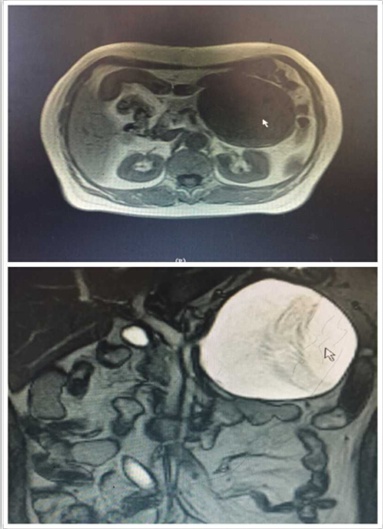

近日,我院肝膽外科入住一位65歲老年女性患者。該患者是一位退休工人,平日生活樸素,一年前自覺有上腹部隱痛不適,每次腹痛發(fā)作便自行于藥店買藥“治療”。可是近段時間,該患者感覺腹痛進(jìn)行性加重,腹部出現(xiàn)隆起,進(jìn)食少量食物便會出現(xiàn)腹脹、惡心、嘔吐不適,遂來我院就診。門診行腹部CT檢查發(fā)現(xiàn)胰腺巨大占位性病變(圖1),此時患者才恍然大悟,立即入住肝膽外科進(jìn)行治療。

圖1